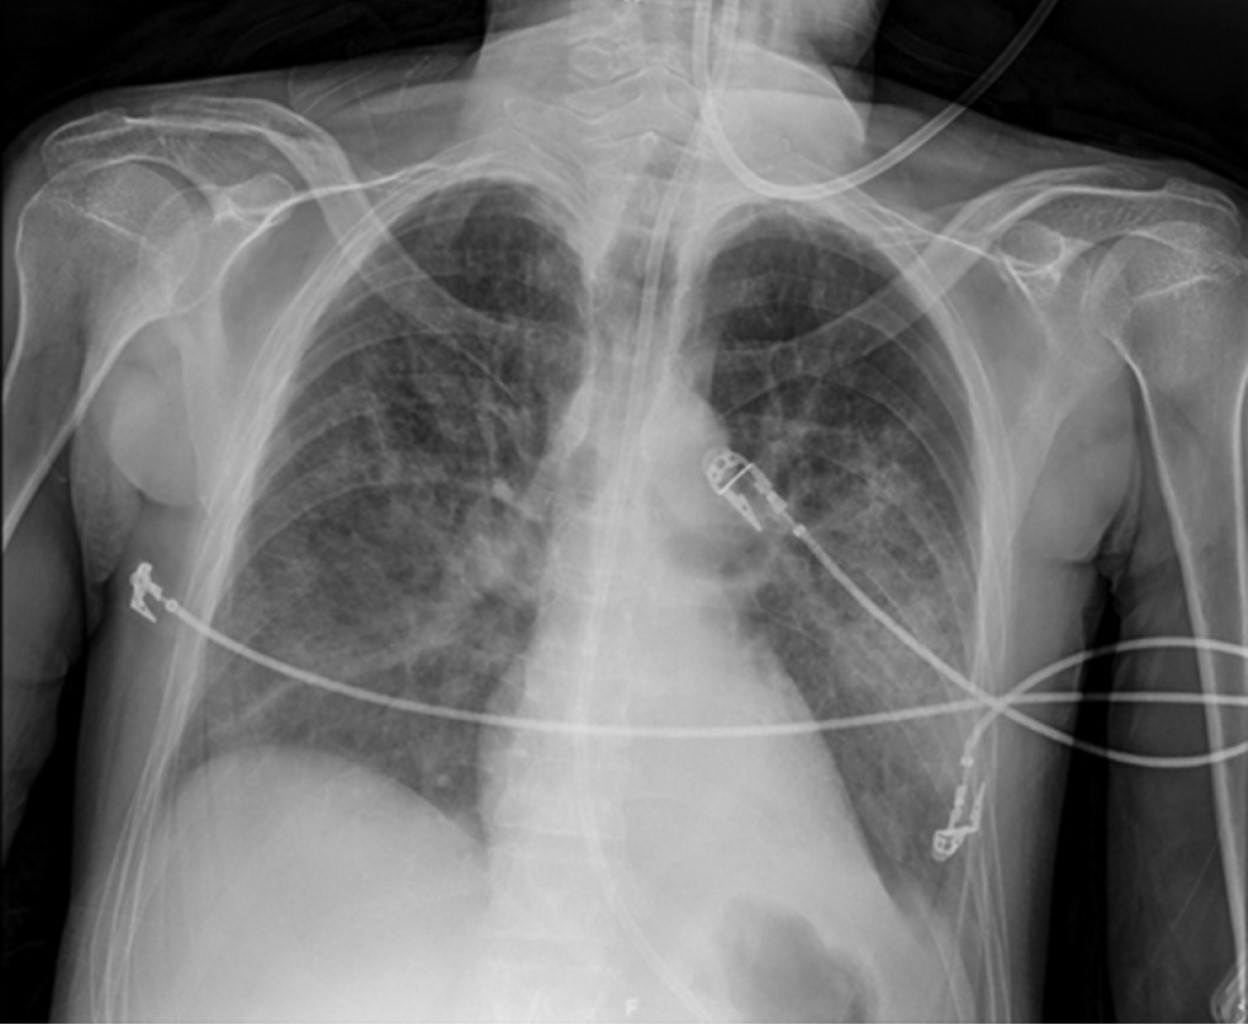

Figura 2